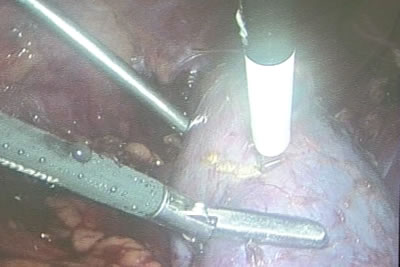

Окончательный этап отсечения участка почки.

Опухоль почки резецирована.

Опухоль с удаленной паранефральной клетчаткой сразу погружается

в пластиковый мешок.

Опухоль с удаленной паранефральной клетчаткой сразу погружается

в пластиковый мешок.

Мешок "затягивается" и удаляется наружу через

разрез.